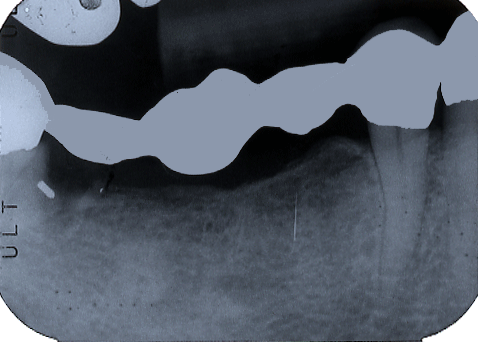

2006.11.29 |45と左下6にインプラント